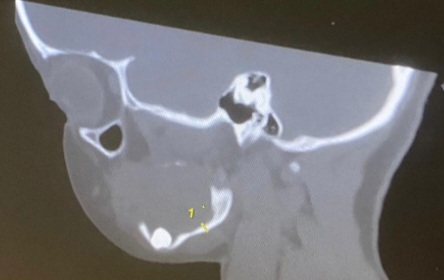

نواكشوط(وكالة السواحل للأنباء):استطاع جراحون بالمستشفى العسكري بنواكشوط استئصال ورم نادر وكبير الححم، لطفلة تبلغ من العمر عشر سنوات.

وكانت الطفلة تشكو آلاما شديدة في الفك، تصاحبها صعوبة المضغ، والسبب هو هذا الورم المسمى "الآرومي المينائي Ameloblastome Mandibulaire".